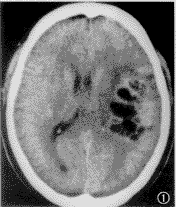

图15 复查ct显示第四脑室及中脑导水管内积血消失,脑水肿消退